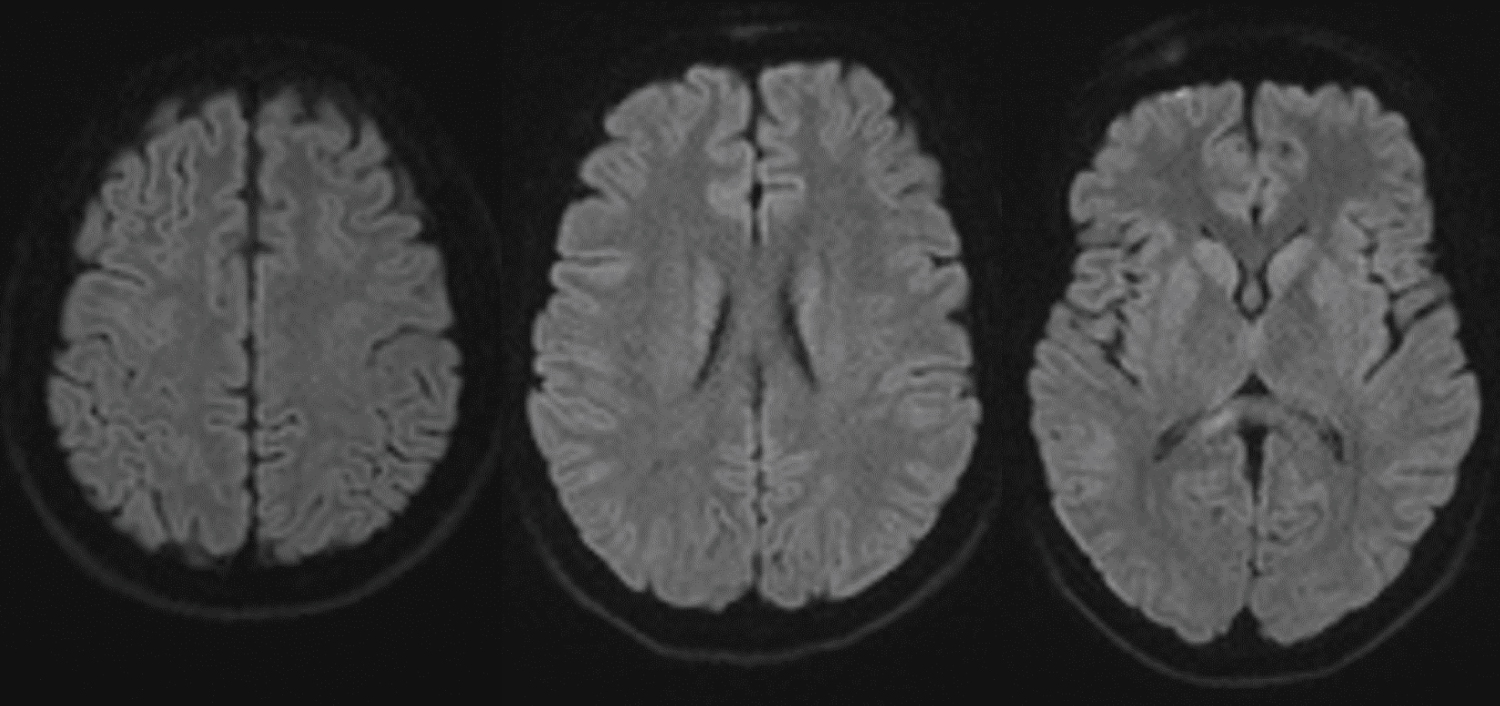

A 20-years-old male was admitted to our emergency department for a road car accident with a diagnosis of bilateral lower extremities fractures (tibial shaft fracture and femoral neck fracture. After six hours he underwent a surgical intervention of endomedullary nailing for both fractures (Figure 1). Before surgery, this patient was conscious at all times but 24 hours after surgery, he manifested state of confusion, with episodes characterized by delusional ideation, confabulation and psychomotor agitation. On neurological physical examination, the patient was alert, disoriented in time, cranial nerves appeared uninjured, and there were no focal limb signs. Brain CT scan and electroencephalogram showed no abnormalities. Due to the persistence of the symptomatology, MRI of the brain was performed, which showed multiple, millimeter-long areolae of pathological signal restriction in DWI study sequences at the bilateral nucleocapsular region, corona radiata, deep white matter and juxtacortical on both sides as well as at the posterior frontal cortical site. Additional similar areas were found at the posterior median and paramedian right commissural region and at bilateral retro trigonal site. These findings were compatible with multiple embolic-based ischemic foci in an evolving phase (Figure 2). There is no specific treatment for fat embolism or fat embolism syndrome. Therapy included prophylaxis stroke with aspirin at a daily dose of 100 mg, Low Molecular Weight Heparin (LMWH) 4000 IU once day and Dexamethasone 4 mg intravenous twice daily. After one day, the patient appeared markedly improved, alert, conscious and cooperative, oriented in time, with fluent speech, normal pupillary reflex, preserved strength, sensitivity and coordination, absent meningeal symptoms. The patient during hospitalization practiced echocardiographic "bubble-test" with evidence of suspected atrial septal defects (ASDs) at the level of the caval septum with left-to-right shunt and passage of microbubbles of moderate entity. Transesophageal echocardiography could not be performed because of the patient's difficulty in lying lateral decubitus. After 10 days, the patient repeated brain MRI that showed attenuation of known ischemic lesions (Figure 3).

Figure 3: MRI FLAIR imaging after 10 days: Improvement of hyperintensity of known cerebral lesions. View Figure 3